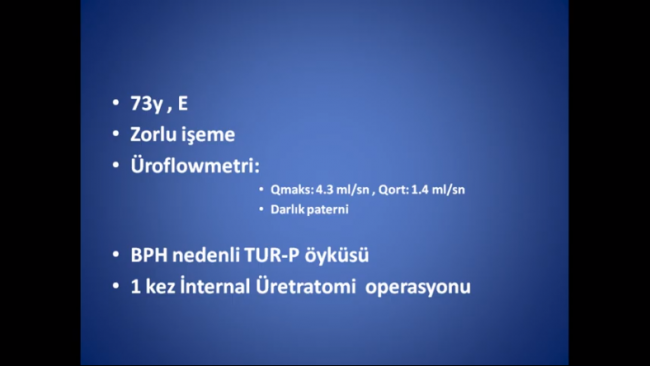

Notice: Trying to access array offset on value of type null in /home/u9176434/en.uretradarligi.com/wp-content/plugins/js_composer/include/autoload/vc-shortcode-autoloader.php on line 64 Notice: Trying to access array offset on value of type null in /home/u9176434/en.uretradarligi.com/wp-content/plugins/js_composer/include/autoload/vc-shortcode-autoloader.php on line 64 Notice: Trying to access array offset on value of type null in /home/u9176434/en.uretradarligi.com/wp-content/plugins/js_composer/include/autoload/vc-shortcode-autoloader.php on line 64 Ventral buccal mucosal urethroplasty ÖZGEÇMİŞ Yaş: 64…